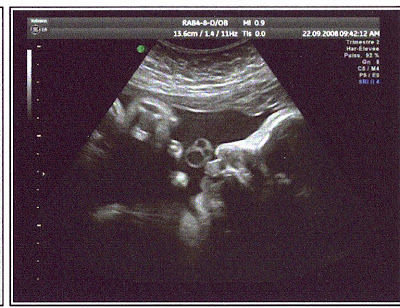

La dernière échographie

Aujourd'hui c'était le jour où il fallait être belle, j'ai passé ma dernière échographie. Malheureusement, les photos ne sont pas très bien (faut dire que je prends de la place!!!). Je vous montre quand même ma trombine pour le plaisir.

Ce qui est vraiment dommage, c'est que toutes les conditions étaient réunis pour faire une photo en 3D (le bon médecin, la bonne salle d'écho et moi), mais c'est justement moi qui n'était pas bien placé, le nez contre la paroie tout écrasé, pourtant le médecin à essayé deux fois mais n'a pas fait de cliché.

Là je suis de profil et j'avais le cordon dans la main.

Ca m'amuse bien le cordon.

Alors, pour tout vous dire, je pèse 1,985 kg. J'ai bien la tête en bas et mon dos se trouve à droite. Mon age gestationnal théorique est de 33,2 semaines. Je ne sais pas trop combien je mesure mais je suis de taille moyenne d'après le médecin.

A priori à terme je devrais atteindre le poids de 3,100 kg. Ce qui a impressionné ma maman.

Une autre petite chose: j'ai des cheveux! Bah oui ça arrive....

Voilà j'ai tout dit et c'est décidé, je reste encore un peu au chaud dans le ventre de ma maman.